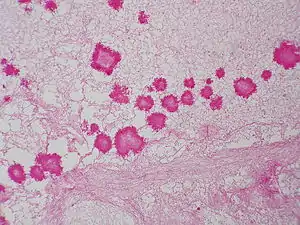

The diagnoses of geotrichosis cannot be determined without using culture or microscopic measurements.[5] The laboratory diagnosis of geotrichosis involves collected fungi samples areas of infections without contamination.[6] Scraping of the mouth lesions and the ulcers can provide a sample of G. candidum. Samples can also be collected from pus and mucus can be obtained from the feces.[5] Sputum can be searched for the mucoid-like white flakes for further examination.[6][5] Culturing the cylindrical barrel-shaped or elliptical fungi in considerable numbers in oral lesions is an indicator that a patient may have geotrichosis.[6] Under the microscope the fungi appears yeast-like and septate branching hyphae that can be broken down into chains or individual arthrospores. Arthrospores appear rectangular with flat or rounded ends.[3][5] Under the microscope the arthroconidia size range from 6-12μm x 3-6μm. Arthroconidia and coarse true hyphae can be observed can be observed under the microscope.[3] Another identification method for G. candidum is selective isolation method. A selection isolation method based on the fungi tolerance to novobiocin and carbon dioxide can determine if G. candidum is the cause of illness.[2]